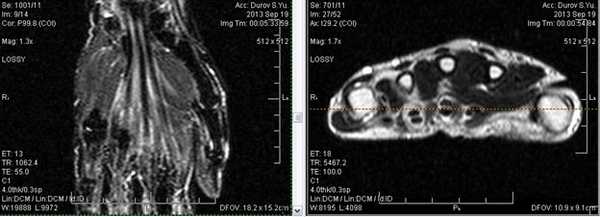

Липома сухожилия

Клинически: Отек левой руки, сохраняющийся длительное время, в настоящий момент пациент начал жаловаться на нарушение чувствительности боковых трех пальцев.

Капсулированная масса прикреплена к сухожилиям поверхностного и глубокого сгибателей указательного пальца. Липома из сухожилия (гистологически доказано).